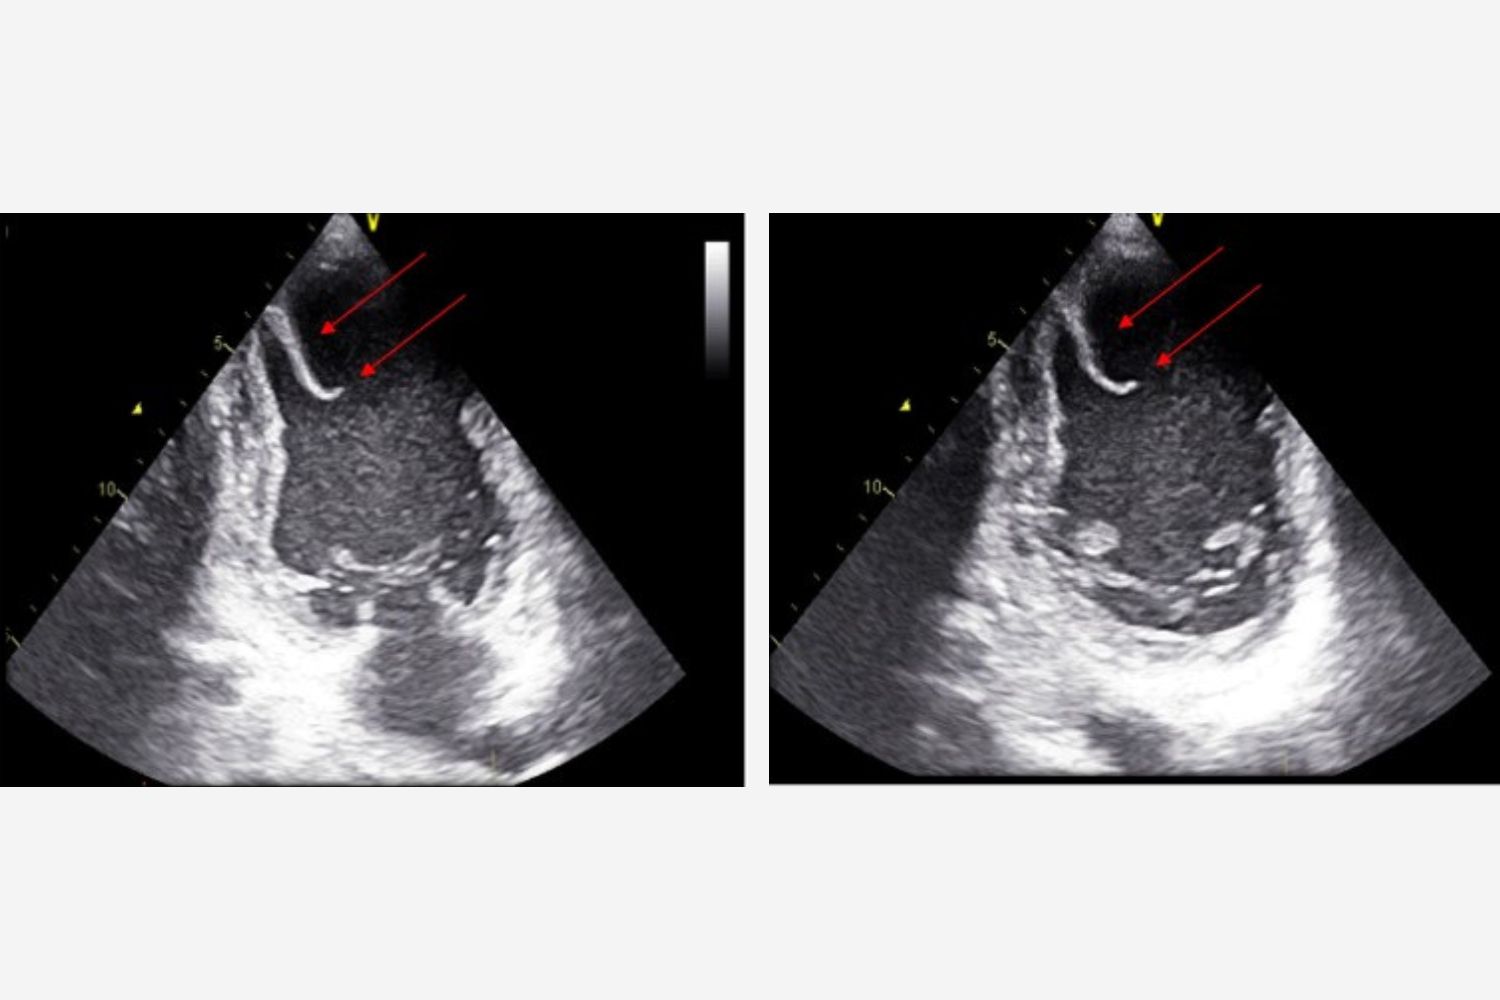

Image of the Week - 5 November 2025